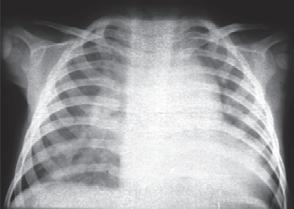

• RTG hrudníku: kardiomegalie, zvýšené prokrvení plic a edém plic (→ obr. 1.6)

• Echokardiografie: přímé zobrazení PDA a diastolického zpětného průtoku v pulmonální arterii s odhadem velikosti zkratu

Obr. 1.6 RTG hrudníku při perzistujícím ductus arteriosus s kardiomegalií a zmnoženou plicní kresbou, zejména centrálně

n Léčba

Cíl: uzávěr ductus arteriosus, který by měl následovat 7.–10. den života, s cílem snížit incidenci chronických následků; např. bronchopulmonální dysplazie.

Farmakologická léčba: inhibitory prostaglandinů (např. indometacin) mohou ovlivnit uzávěr ductus arteriosus. Kontraindikací farmakologické léčby jsou trombocytopenie a nedostatečnost ledvin.

Operační léčba: při kontraindikaci podání indometacinu nebo při selhání farmakologické léčby je indikován chirurgický uzávěr PDA.

POZOR

Včasný uzávěr ductus arteriosus je obzvláště důležitý u pacientů s významnou oběhovou nestabilitou.